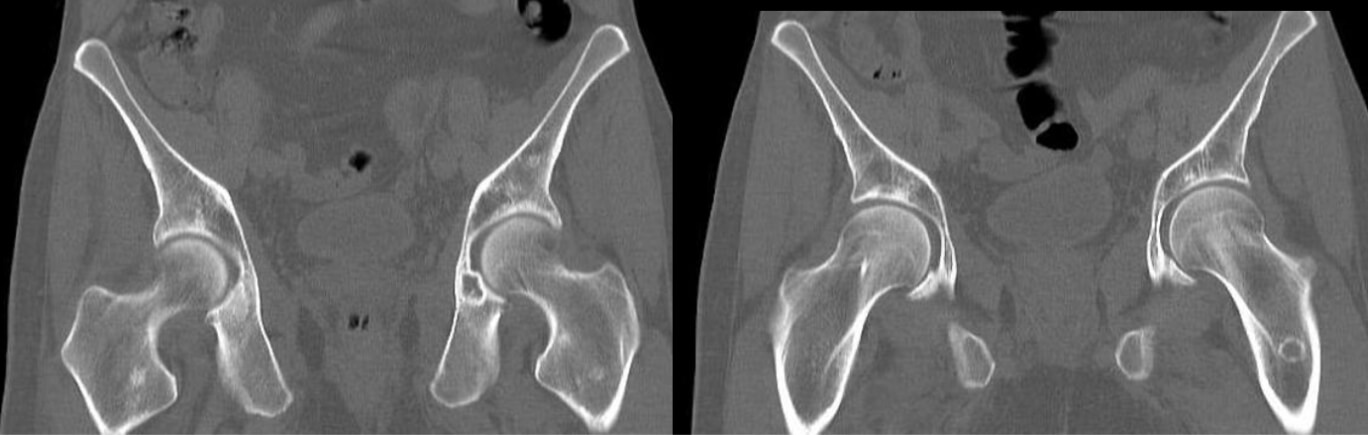

Результаты компьютерной томографии органов грудной клетки, брюшной полости и малого таза с внутривенным контрастированием убеждают вас в наличии у пациентки диссеминированного характера заболевания с метастатическим поражением костей:

Рис. 2 — МСКТ органов малого таза с внутривенным контрастированием. Отмечается литическое поражение левой вертлужной впадины, правой вертлужной впадины, проксимального отдела бедренной кости.

Картина смешанного (бластического и литического) поражения была обнаружена в зоне крестца и в области поясничного отдела позвоночника:

Рис. 3 — МСКТ органов малого таза с внутривенным контрастированием. Отмечается литическое и склеротическое поражение скелета области крестца и поясничного отдела позвоночника.